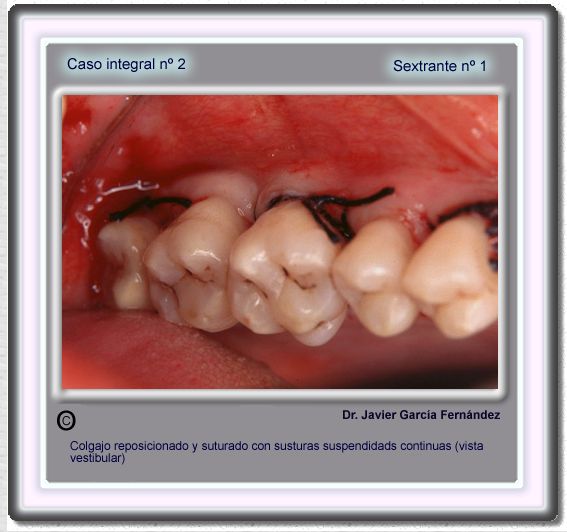

image 29